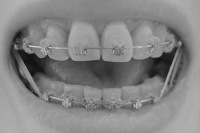

前から見たところ。特に変化なし。

2008/5/20撮影